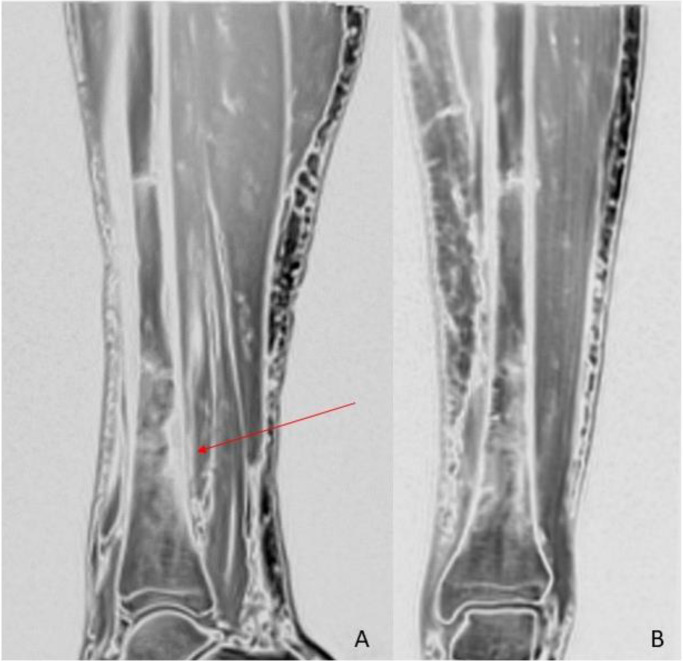

MRI of the left leg (Fig. 1, Fig. 2, Fig. 3) showed bone marrow edema extending from the middle to the distal third of the tibial diaphysis. In the posterior middle-third of the tibial diaphysis, serpiginous subcortical images with oblique course and flow-voids on T1- and T2-weighted were seen. Similar findings were visible at the distal third of the tibial diaphysis. These findings were consistent with dilated vessels connected to anomalous venous structures with an intra-osseous course. At the cortical entry point of the distal third of the tibial diaphysis, periosteal reaction on the posterior side was visible. These intraosseous venous structures were connected to deep venous branches at the middle third of tibia. Small superficial varicose veins were also visible at the medial side of the leg. Subcutaneous edema was present.

Fig. 2.

Magnetic resonance (A and B) sagittal and coronal high resolution isotropic VIBE images showing periosteal reaction at the distal third of the tibial diaphysis associated with bone marrow edema (red arrow).

Fig. 3.

Magnetic resonance axial T2-weighted images showing a serpiginous structure entering the bone from a cortical entry point at the distal third of the tibial shaft.